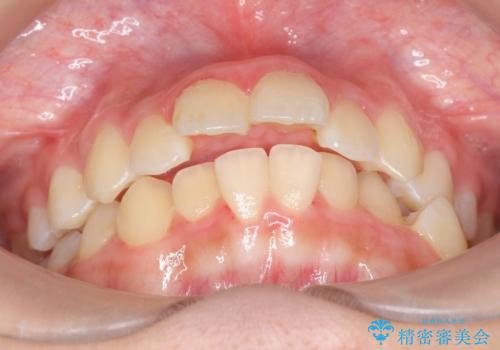

- 前歯のねじれを主訴に来院。

マウスピース矯正も検討されましたが、マウスピースの取り外しがライフスタイルに合わないということで、ワイヤー矯正を選択されました。

生まれつき下顎の前歯が3本でした。(本来は4本)。上の前歯をそのまま並べると出っ歯になってしまうのでディスキングを行い、上下の前歯がかむようにしました。

また、左上第二大臼歯が頬側転位していたのも治しました。

審美ブラケットとホワイトワイヤーで、ワイヤー矯正でも目立たず治療が可能です。